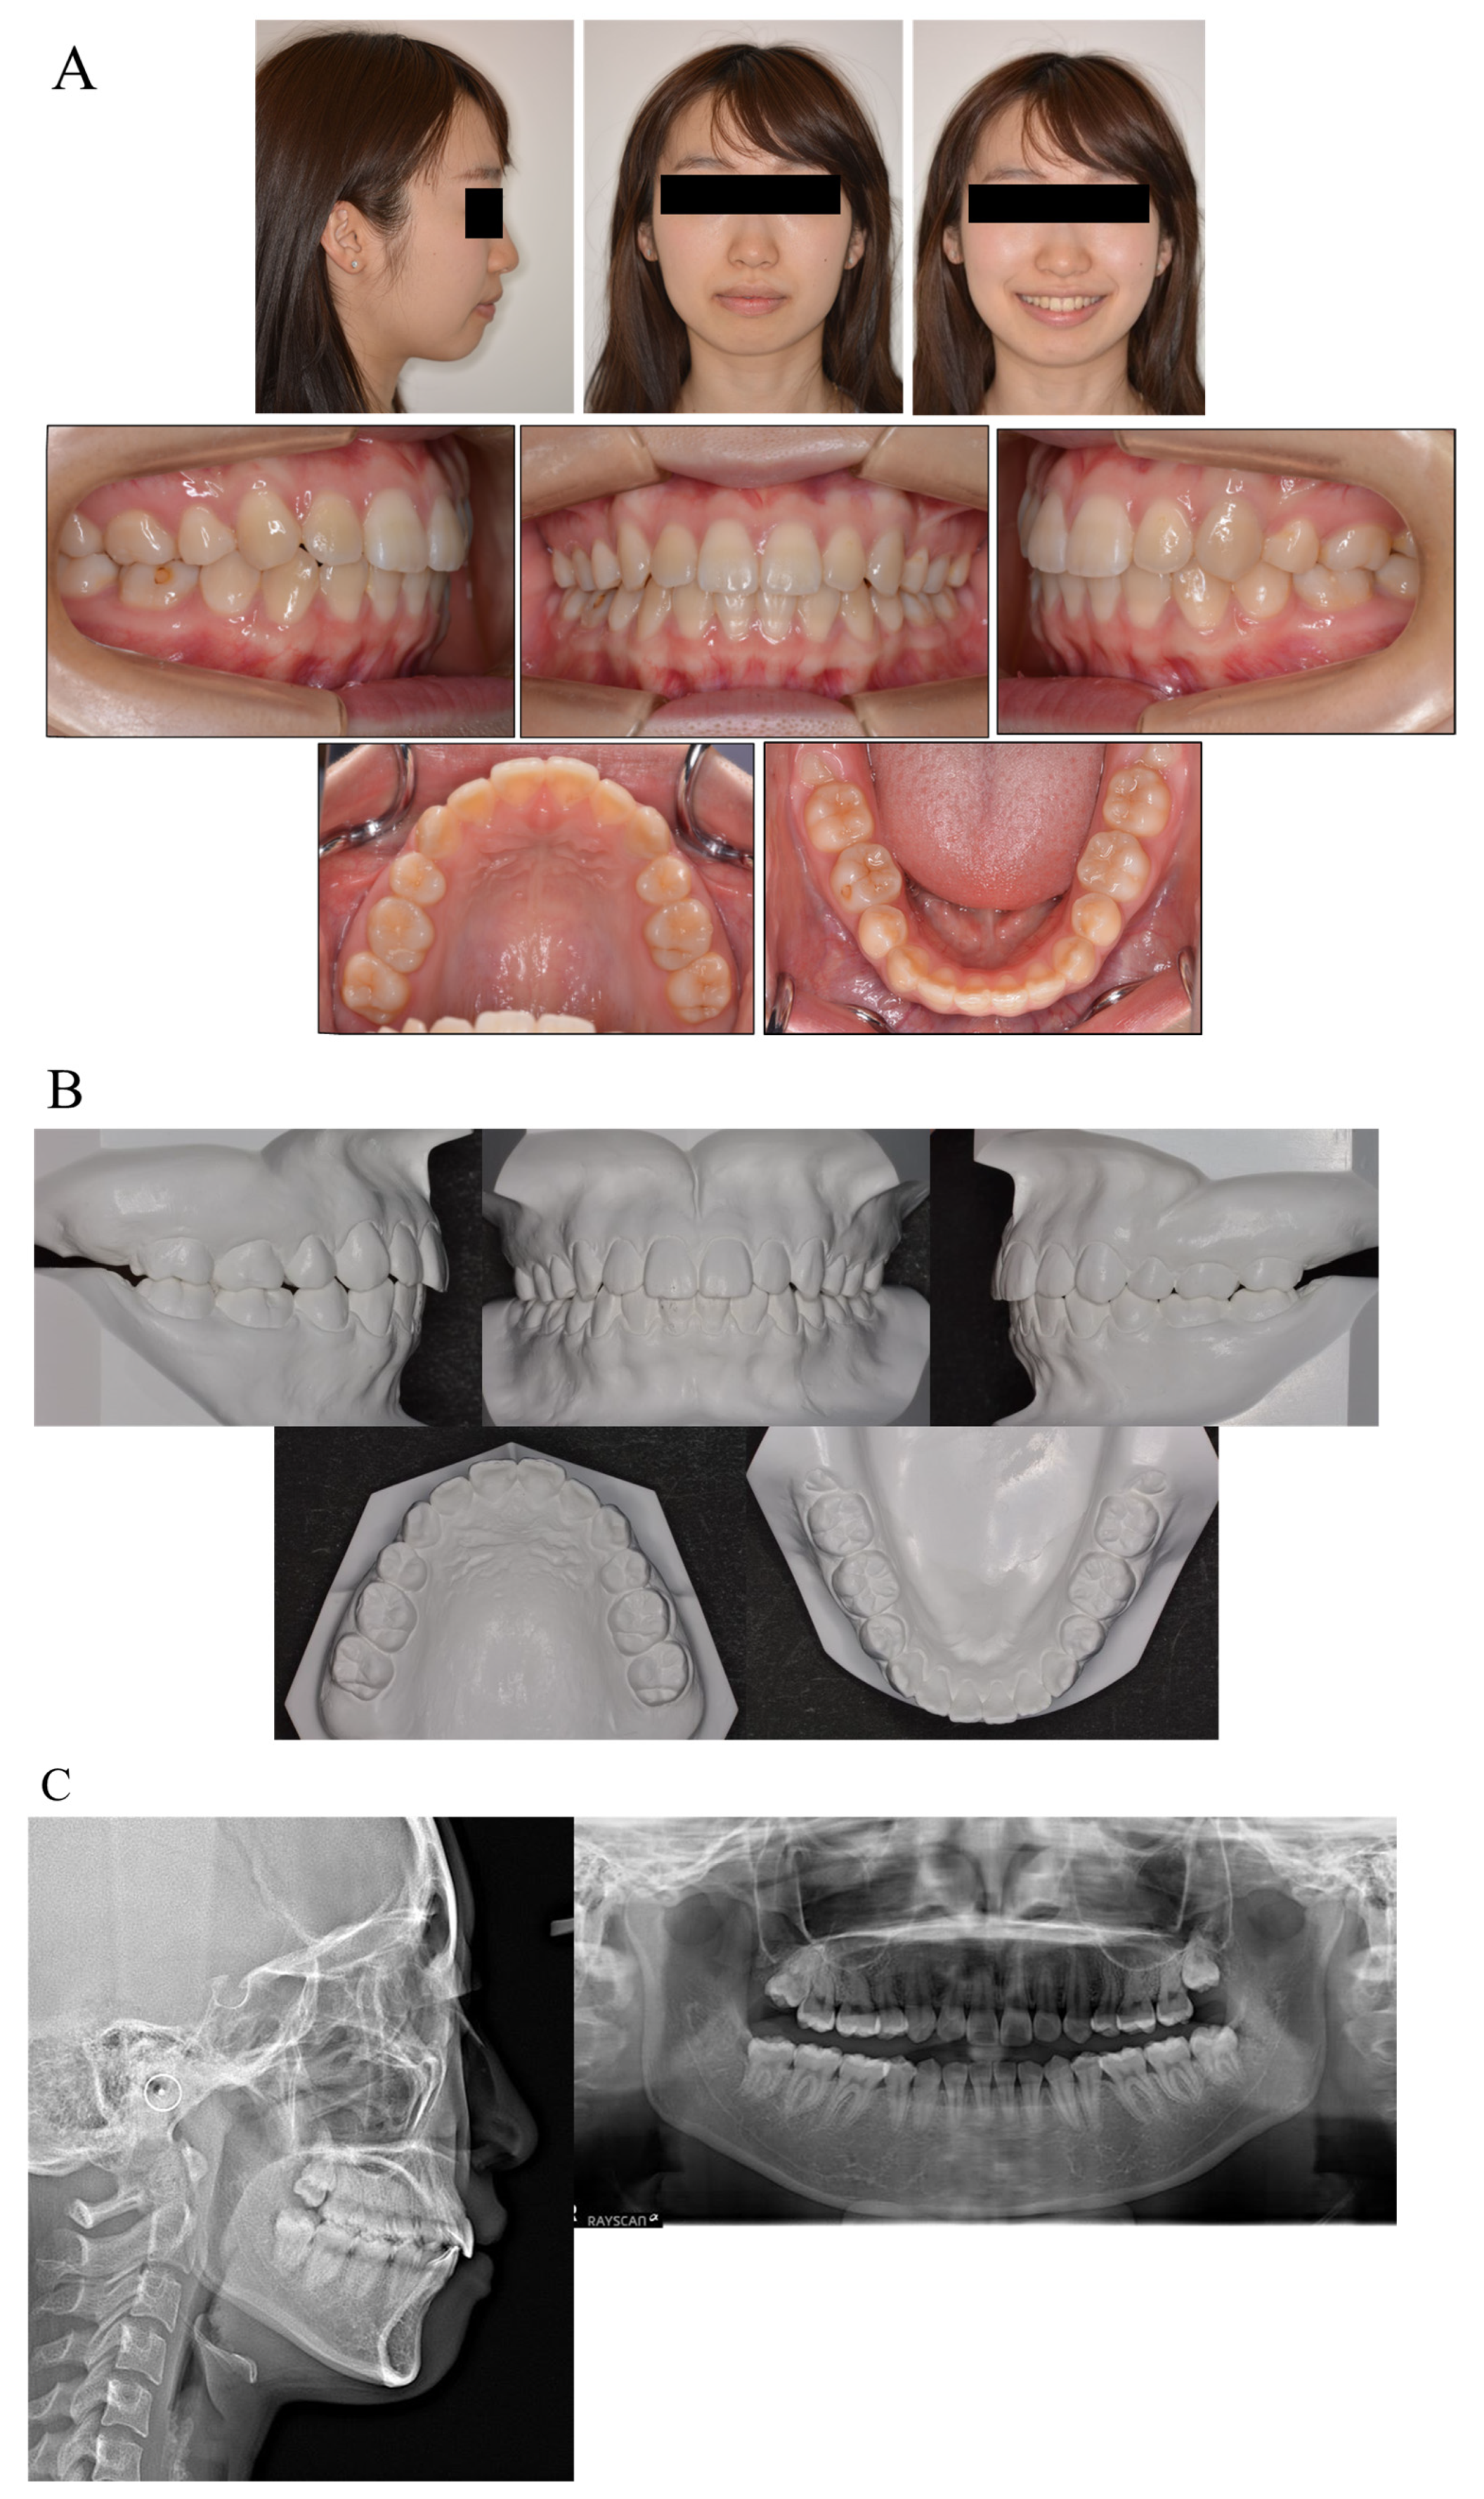

The patient showed an acceptable occlusion and good facial profile (i.e., balanced lip line), owing to the successful retraction of the upper canines and anterior teeth. The dental arches were aligned and leveled, and an ideal overjet and overbite were achieved (Figure 3).

Figure 3.

Facial and intraoral photograph (A), dental casts (B) and radiographs ((C) lateral cephalogram; panoramic radiograph) of post-treatment (patient is 17 years old).

Although the detailing of the treatment took some time, the total duration of the treatment was 13 months. Both the upper and lower lips recessed, and the patient’s facial profile was considerably improved. The postoperative panoramic radiograph identified a slight root resorption and no problem with root parallelism. The postoperative cephalometric analysis in the lateral view demonstrated changes in the FMIA (44.2 to 57.2) and interincisal angle (110.7 to 136.1), which contributed to an improvement in the facial profile.